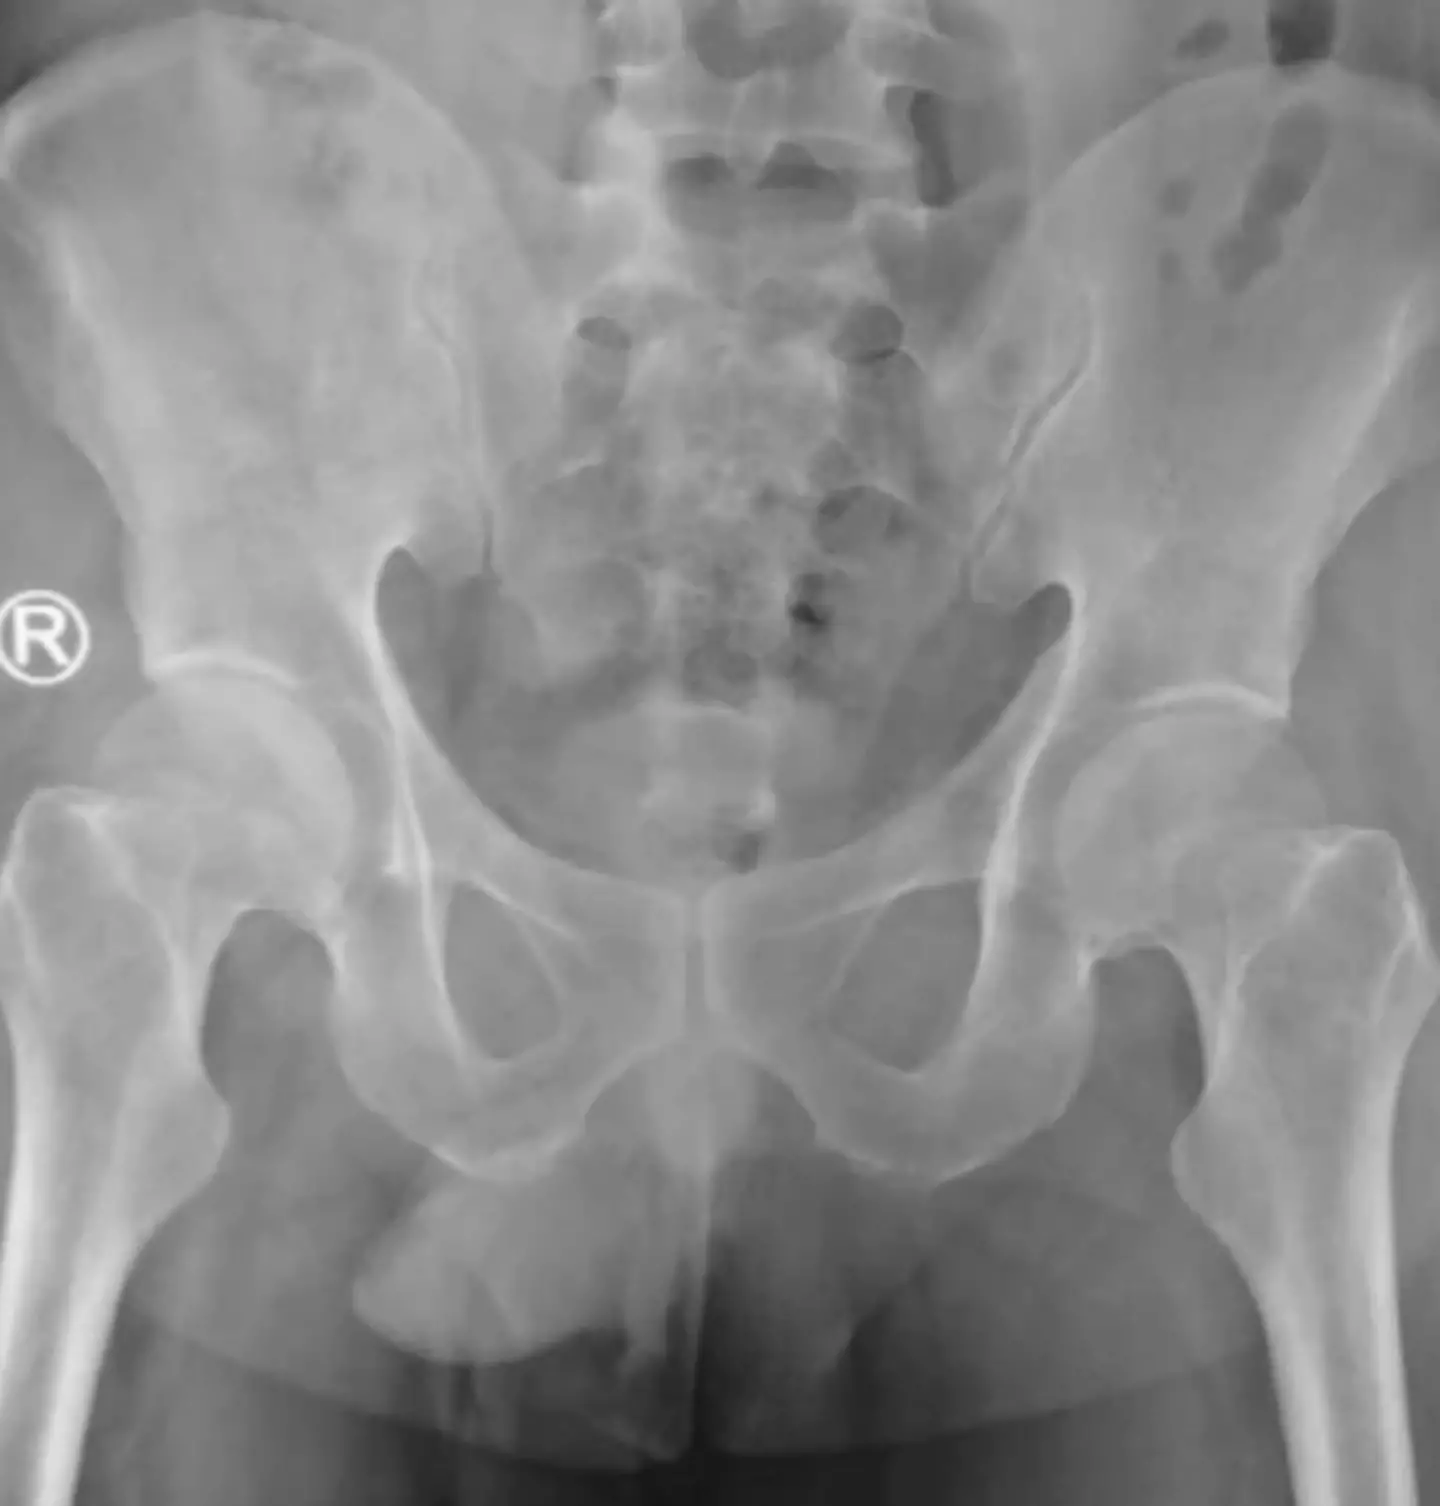

After experiencing problems urinating and severe abdominal pain which lasted for two hours, the man went to a hospital in Surabaya, Indonesia.

After an unsuccessful first attempt to remove the string, doctors decided to insert a camera into the man's bladder. This showed a 'black bundle of string' which meant that medics were able to use forceps after giving him local anaesthetic.